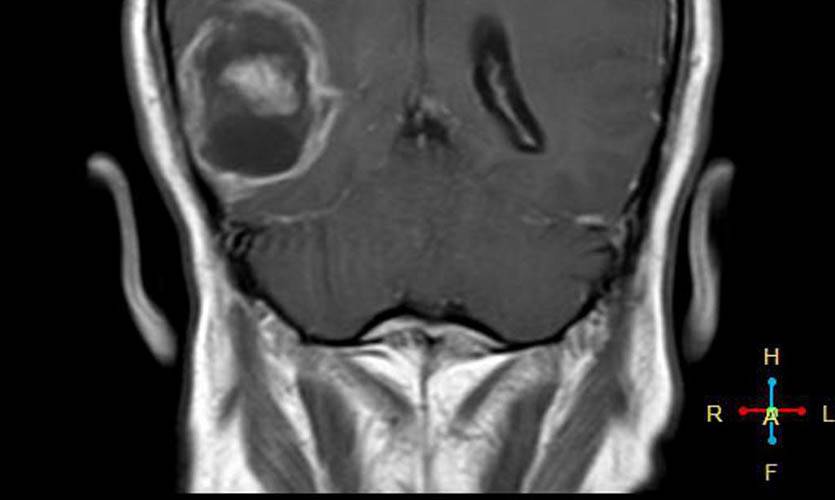

Для анализа случаев заболевания использовался массив данных из семи европейских стран INTERPHONE (Дания, Финляндия, Германия, Италия, Норвегия, Швеция и юго-восточная Англия).

Было проведено исследование радиочастотных электромагнитных полей путём оценки общей кумулятивной дозы удельной энергии (TCSE) для каждого человека. Для каждого случая местоположение опухоли определяли нейрорадиологами, а центр опухоли оценивался компьютерным алгоритмом или непосредственно нейрорадиологом.

Для каждого случая средняя точка опухоли на трехмерной сетке определялась на основе радиологических изображений.

По итогам исследования выяснялось, что у пользователей мобильных телефонов наблюдалось повышение шансов появления злокачественных опухолей головного мозга и развития астроцитомы при использовании мобильных телефонов только с одной стороны головы.

Проще говоря, если ваш смартфон лежит ночью с правой стороны (по статистике именно так), то риск появления опухоли возрастает именно справа.